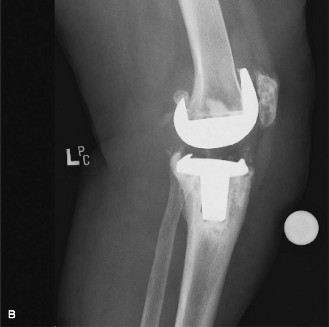

A 65-year-old female presents with a painful, left total knee replacement that was performed 7 years ago. The pain began WITHOUT trauma several months ago and is progressively worsening. She has started to use a walker for ambulation and is becoming increasingly reliant on it. Examination shows a profound varus deformity with varus thrust. Radiographs are shown in Figure 7–9A and B.

Figure 7–9 A–B

The correct answer is (A). When evaluating the painful total knee replacement, it is helpful to divide the etiology of the pain into either intra-articular/intrinsic or extra-articular/extrinsic knee pain. Intra-articular problems include aseptic loosening, malalignment, polyethylene wear, osteolysis, implant failure/breakage, arthrofibrosis, patellar clunk, and extensor mechanism dysfunction. Extra-articular problems include referred pain from the hip or spine, neuroma, complex regional pain syndrome, vascular claudication, soft tissue inflammation (pes anserine bursitis, patellar or quadriceps tendonitis), or periprosthetic fracture. It is always imperative to establish a diagnosis before embarking upon revision surgery as simply “re-doing” surgery without a diagnosis is not likely to lead to improvement of symptoms. This patient’s x-rays demonstrate a periprosthetic fracture with loosening of the tibial component, medial bone loss, and collapse of the proximal medial tibia. This occurred without trauma and was progressive in nature, and thus the fracture likely occurred through a region of osteolysis that was causing progressive medial tibial collapse with concomitant aseptic loosening.